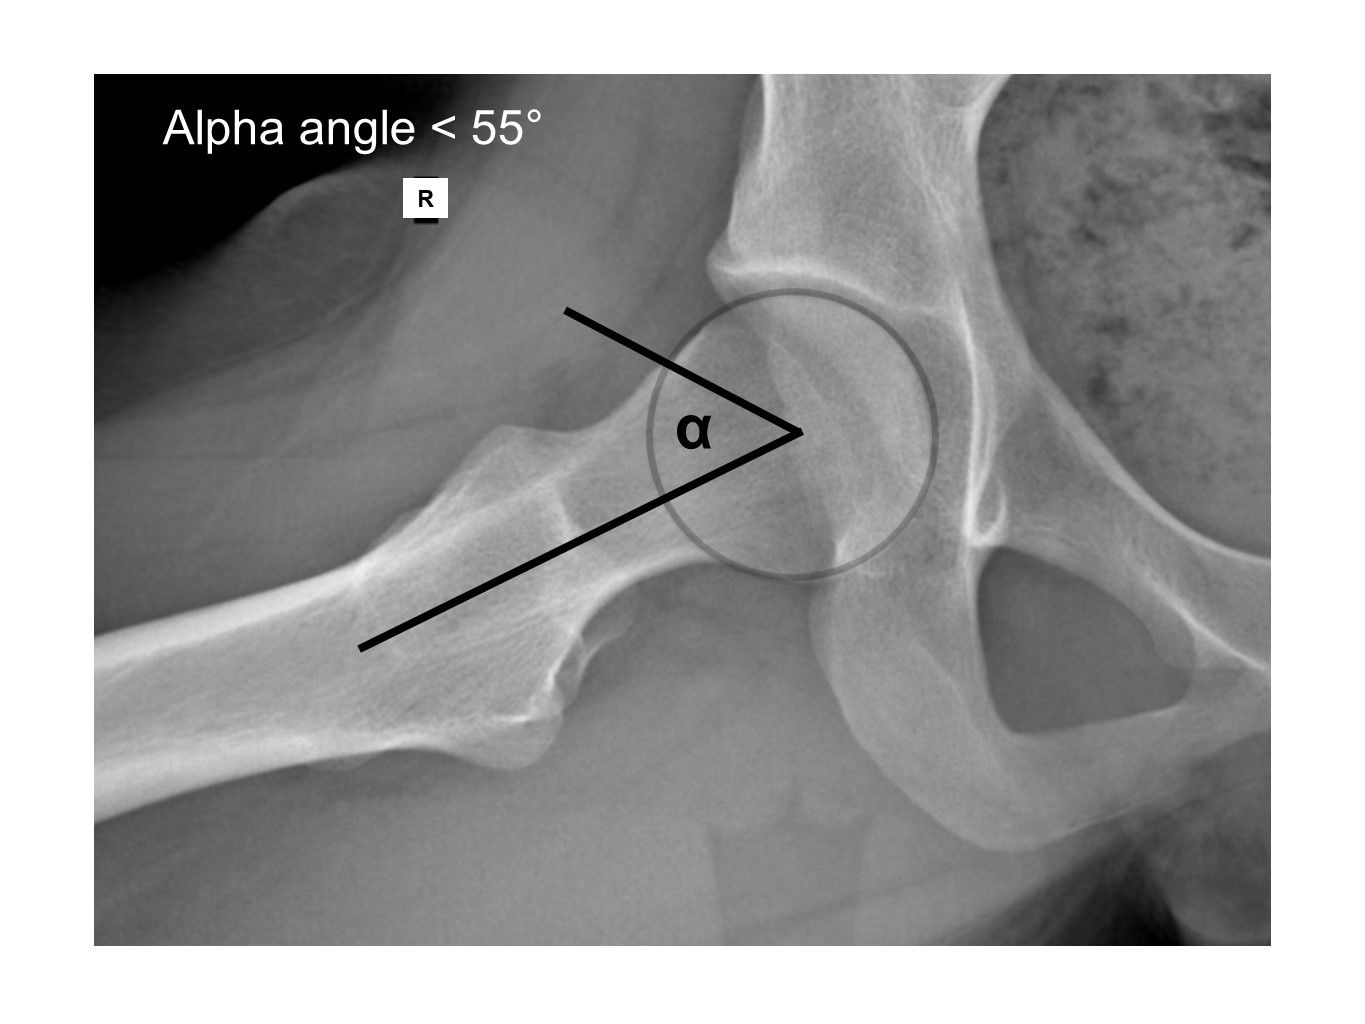

Furthermore, acetabular retroversion can be identified by the posterior wall and/or ischial spine sign. Dunn views should be used to check for any bump that could cause cam impingement. The alpha angle (29) (Fig. 14) should be calculated, and the head–neck junction checked for cysts or any signs of sclerosis.